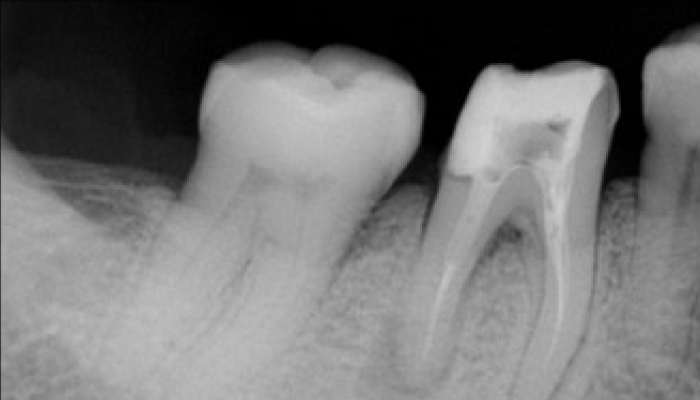

충치치료 전후 사례

• 치료 전

치료 후